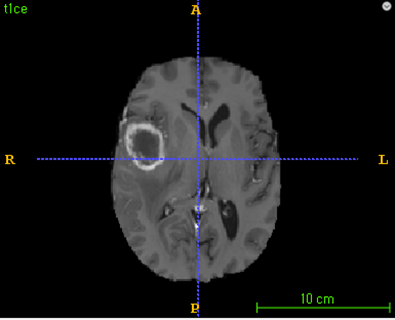

Post-contrast T1-weighted MR image로부터 자동으로 tumor segmentation할 수 있는 알고리즘

1)HGG(high grade glioma) brain tumor 환자의 post-contrast T1-weighted MR image로 부터 Tumor 영역을 자동으로 segmentation할 수 있다.

2)Segmentation 결과는 necrotic tumor core와 gd-enhancing tumor의 영역을 포함한다.